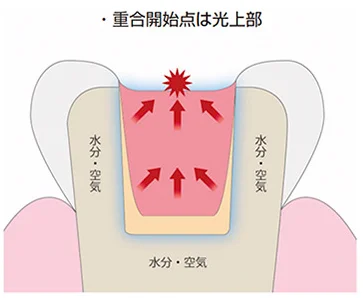

【歯科医師向け】重合収縮のコントロールについて【1級窩洞編】

こんにちは。 今日は表題の通り、患者さん向けではなく、歯科医師向けのブログになります。 現在、レジン充填は全国どころか世界中で行われており、先進国を筆頭に材料も年々進化していき、適用範囲も激しく広がっていってます。 それに対して、医療の現場…